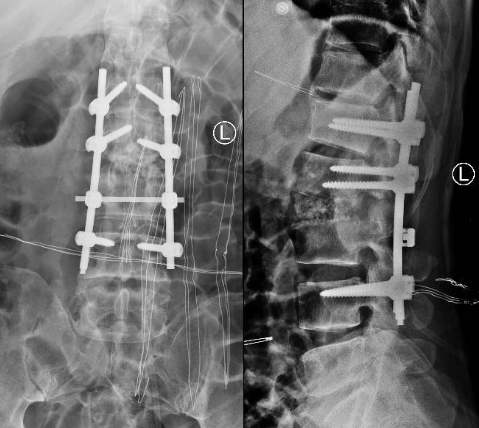

术后X线片

患者出院后感腰部疼痛持续加重,到杏吧原创 门诊就诊,以“腰椎感染”收住入院。患者发病后腰椎CT及MRI均提示腰2-3椎间隙变窄,椎板破坏,综合以上资料诊断”腰椎结核”。入院后经口服四联抗结核药物治疗3周,患者自觉腰部疼痛减轻,午后无发热及盗汗后,在全麻下行颈后路病灶清除、椎间植骨、椎弓根钉棒系统内固定术。手术顺利,术后继续抗结核治疗。患者恢复顺利,术后1周下床活动,无特殊不适。术后2周拆线、出院,院外继续口服抗结核药物治疗,定期门诊复查。